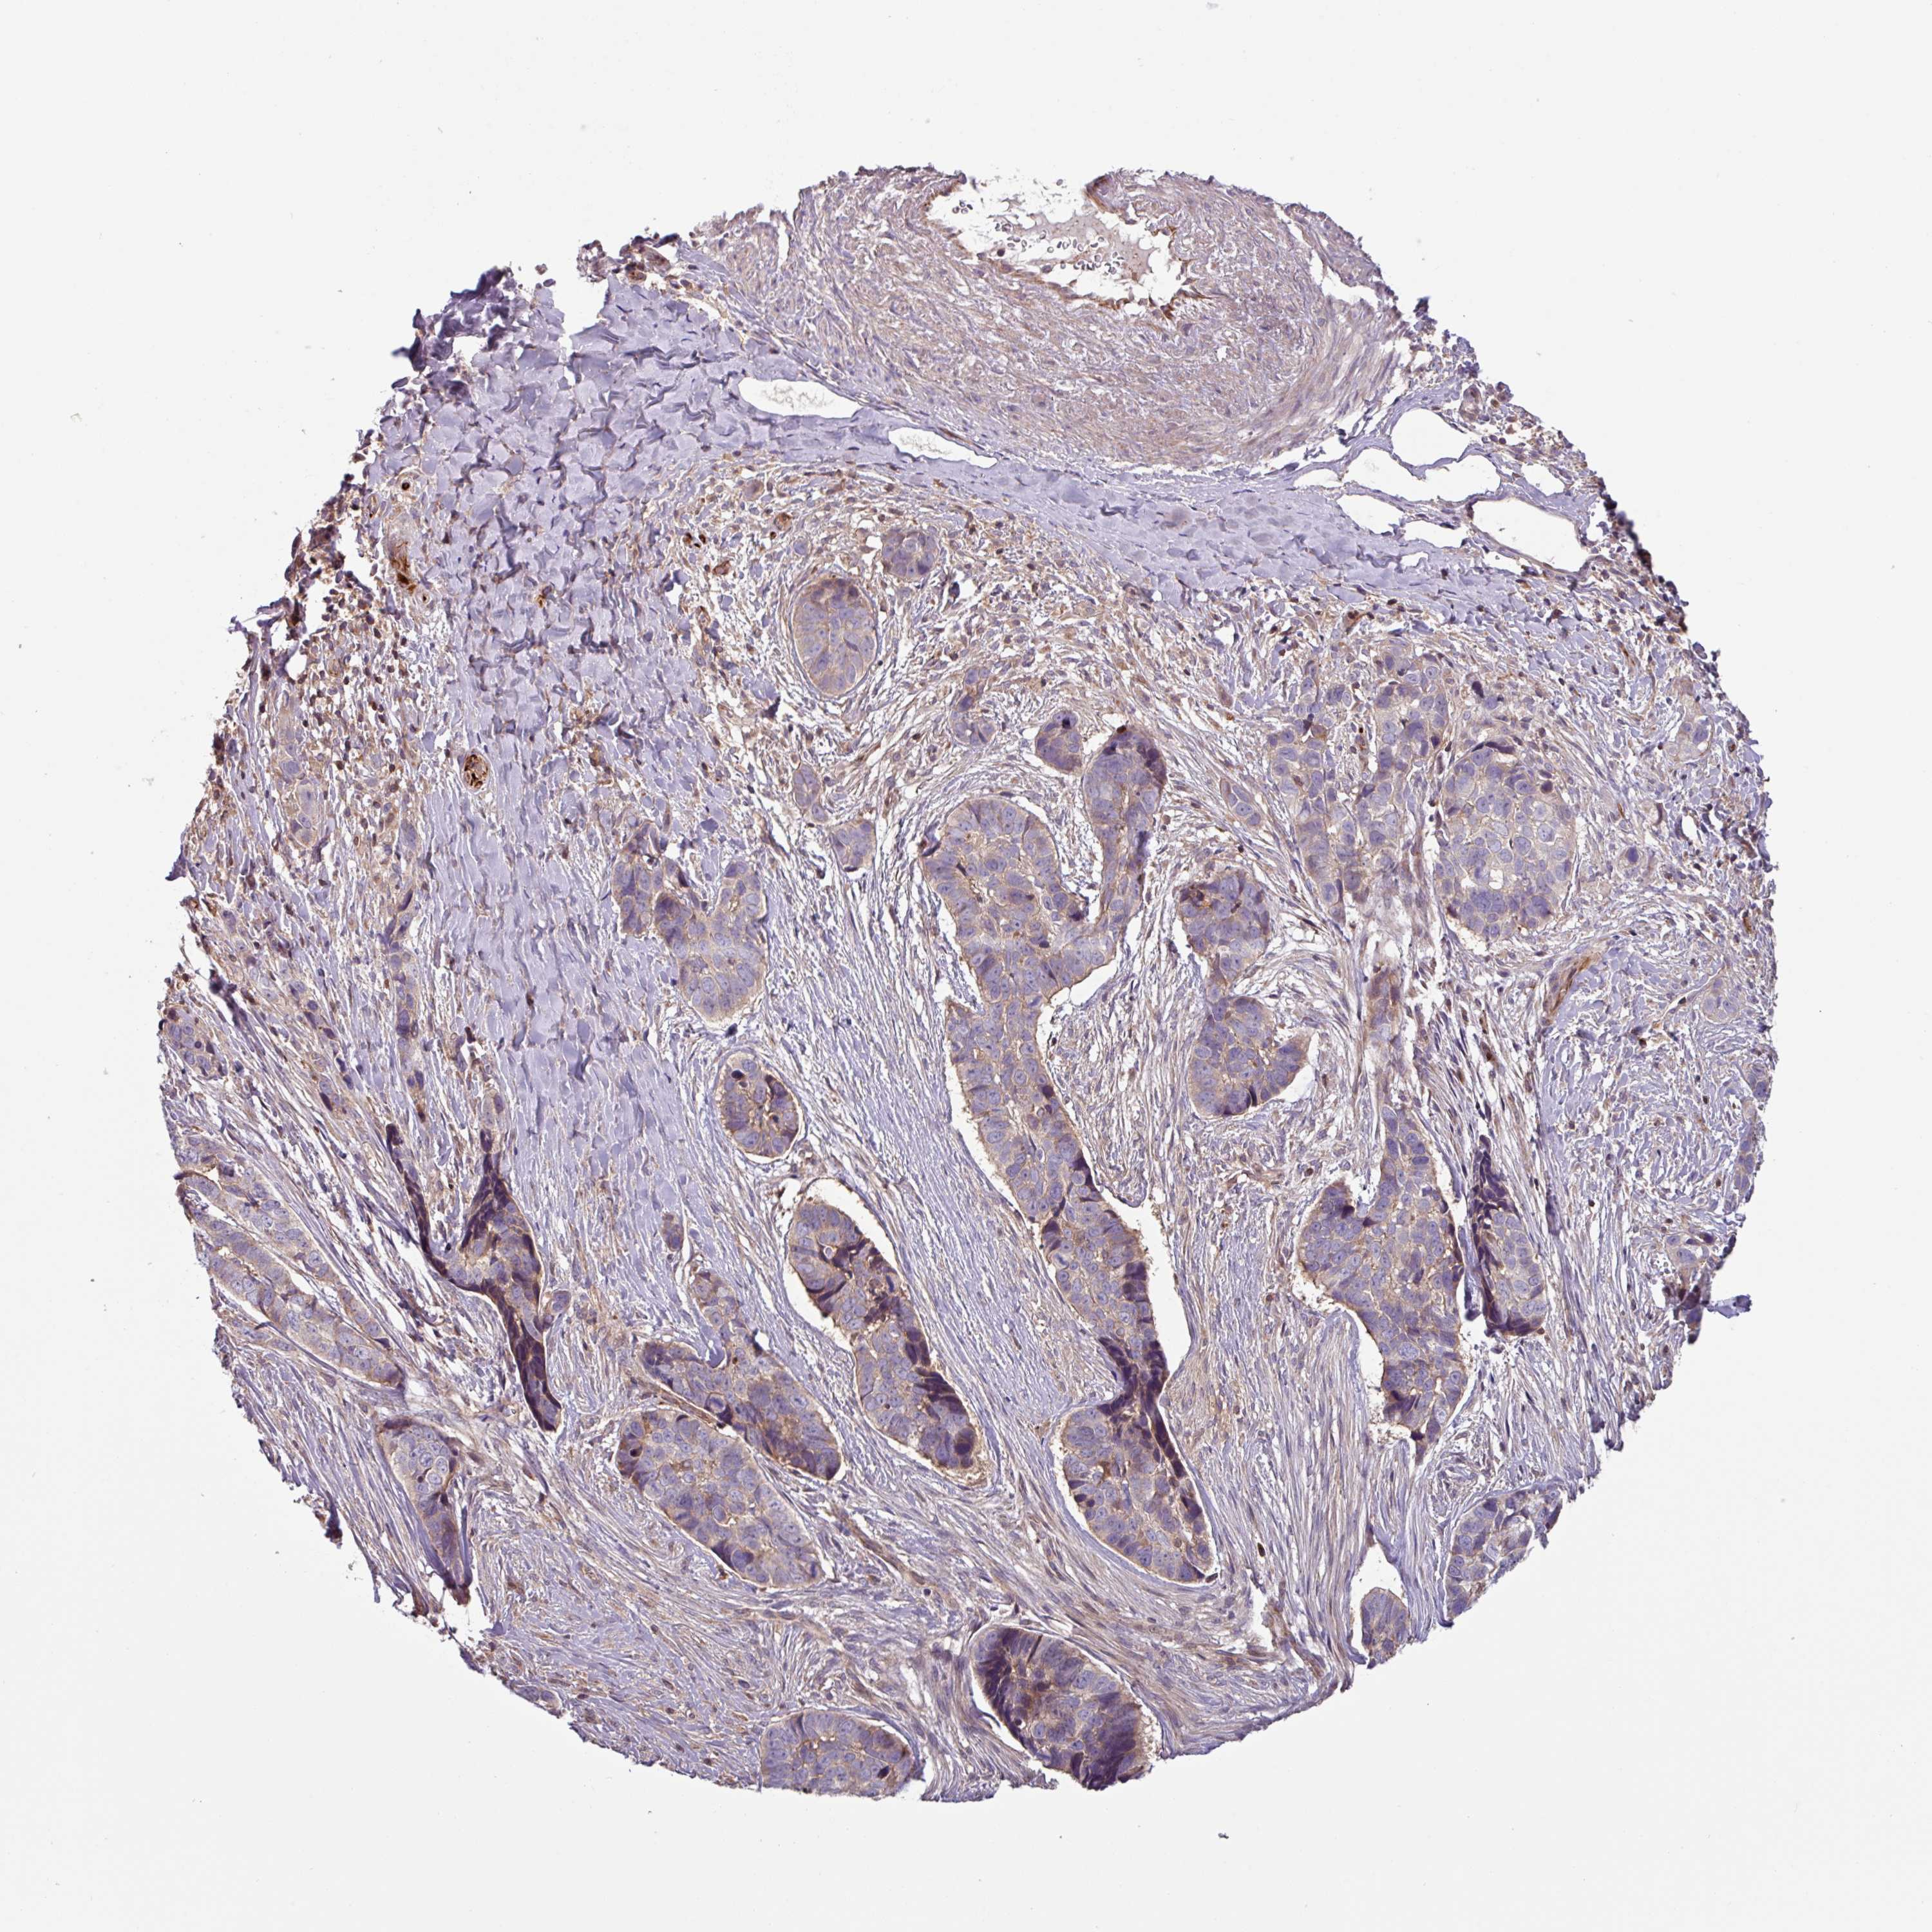

SKIN CANCER - Protein expressioni

A mouse-over function shows sample information and annotation data. Click on an image to view it in a full screen mode. Samples can be filtered based on level of antibody staining by selecting one or several of the following categories: high, medium, low and not detected. The assay and annotation is described here.

Antibody staining in the annotated cell types in the current human tissue is reported as not detected, low, medium, or high, based on conventional immunohistochemistry profiling in selected tissues. This score is based on the combination of the staining intensity and fraction of stained cells.

Each image is clickable and will lead to virtual microscopy that enables deeper exploration of all samples and also displays staining intensity scores, fraction scores and subcellular localization as well as patient and tissue information for each sample.

Antibody HPA051875

Squamous cell carcinoma, NOS